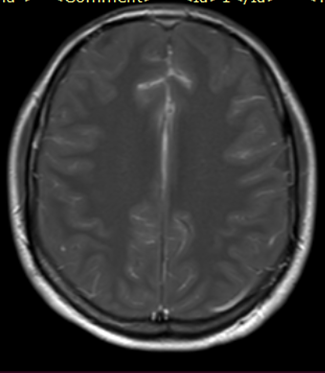

Se solicitó inicialmente Imagen de resonancia magnética (IRM) de columna lumbosacra simple y estudios de neurofisiología. La electromiografía más neuroconducciones de las 4 extremidades reportó neuropatía mielínica de expresión leve del nervio peroneo motor. Imagen de resonancia magnética lumbosacra simple muestra hallazgos compatibles con aracnoiditis adhesiva (figura 1). Ante estos hallazgos, se complementan estudios con resonancia torácica y cerebral con contraste. En la resonancia de columna torácica, se observa incipiente siringomielia (figura 2.) y la resonancia cerebral con contraste no mostró alteraciones.

Figura 1.